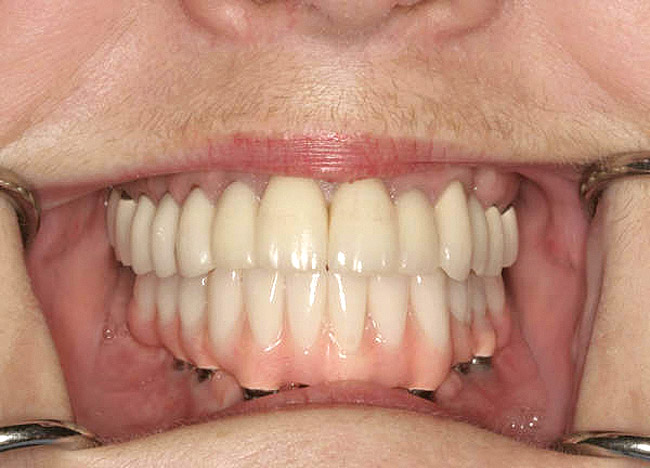

It is also important to explain to patients that the health of their gums is assessed every time they come in; but at this point in time, there are some areas of bleeding on probing, with pockets of disease around their teeth greater than 3 mm deep. It must also be communicated that this is a sign of infection in their gums and that it should be treated immediately (Figure 1).